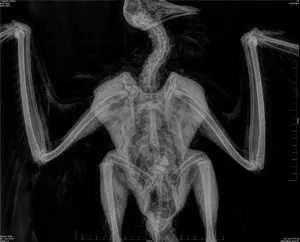

בחברה להגנת הטבע, מציינים כי הרחם שנפגע, הוא פרט צעיר, יליד 2024, שאיננו מקנן עדיין, אך שרד את שנתו הראשונה והיה בדרך להצטרף לאוכלוסייה שדוגרת בישראל. "הרחם המדברי, מוגדר בסכנת הכחדה חמורה בישראל, עם אוכלוסייה בגודל 40 עד 50 זוגות בלבד", אומר ד"ר יואב פרלמן, מנהל מרכז הצפרות של החברה להגנת הטבע. "הוא גם מוגדר בסכנת הכחדה עולמית בדרגה השנייה בחומרתה EN. הרעלות, התחשמלויות, ירי והפרעות, ועכשיו גם פגיעה מטורבינות רוח – דוחקים את האוכלוסייה בישראל, אל עבר הכחדה".

החיוויאי שנפגע הוא נקבה בוגרת, שבסבירות גבוהה נפגעה מלהבי הטורבינות, תוך כדי דאייה וחיפוש מזון עבור גוזליה, כיוון שהחיוויאים עסוקים בדאייה ואיתור הזוחלים על הקרקע ולא מבחינים בלהבי הטורבינות, המסתובבים במהירות עצומה. "עופות דורסים נמצאים בימים אלו בתקופת הקינון", מוסיף נדב ישראלי, צפר בכיר בחברה להגנת הטבע, "ומשמעות הפגיעה בעופות דורסים, במהלך קינון, היא גם הרס הקינון שלהם. לצערנו, נראה שכל החששות שלנו, ההתרעות, האזהרות, כל מה שאמרנו שעלול לקרות, לאורך כל תהליך קידום החווה – מתממש לנגד עינינו".